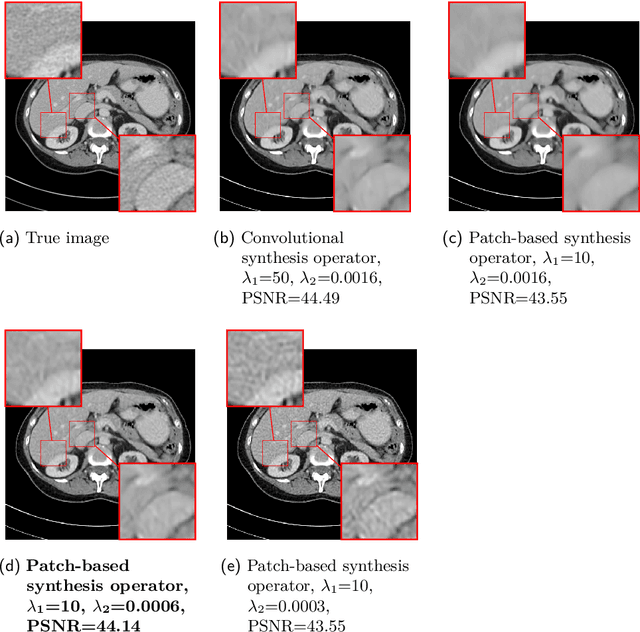

Abstract:This work presents an approach for image reconstruction in clinical low-dose tomography that combines principles from sparse signal processing with ideas from deep learning. First, we describe sparse signal representation in terms of dictionaries from a statistical perspective and interpret dictionary learning as a process of aligning distribution that arises from a generative model with empirical distribution of true signals. As a result we can see that sparse coding with learned dictionaries resembles a specific variational autoencoder, where the decoder is a linear function and the encoder is a sparse coding algorithm. Next, we show that dictionary learning can also benefit from computational advancements introduced in the context of deep learning, such as parallelism and as stochastic optimization. Finally, we show that regularization by dictionaries achieves competitive performance in computed tomography (CT) reconstruction comparing to state-of-the-art model based and data driven approaches.